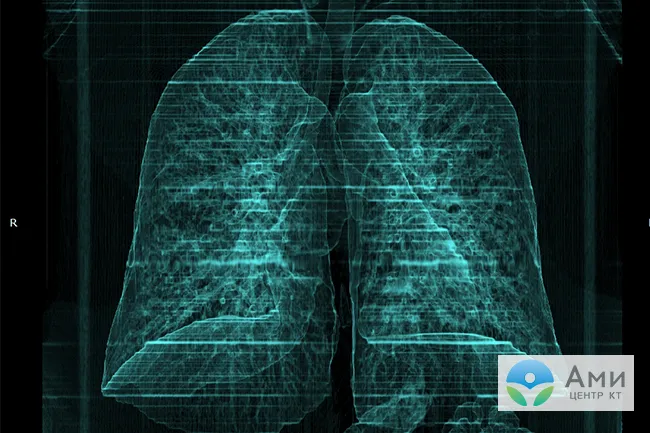

Для сравнения — так выглядят легкие в норме